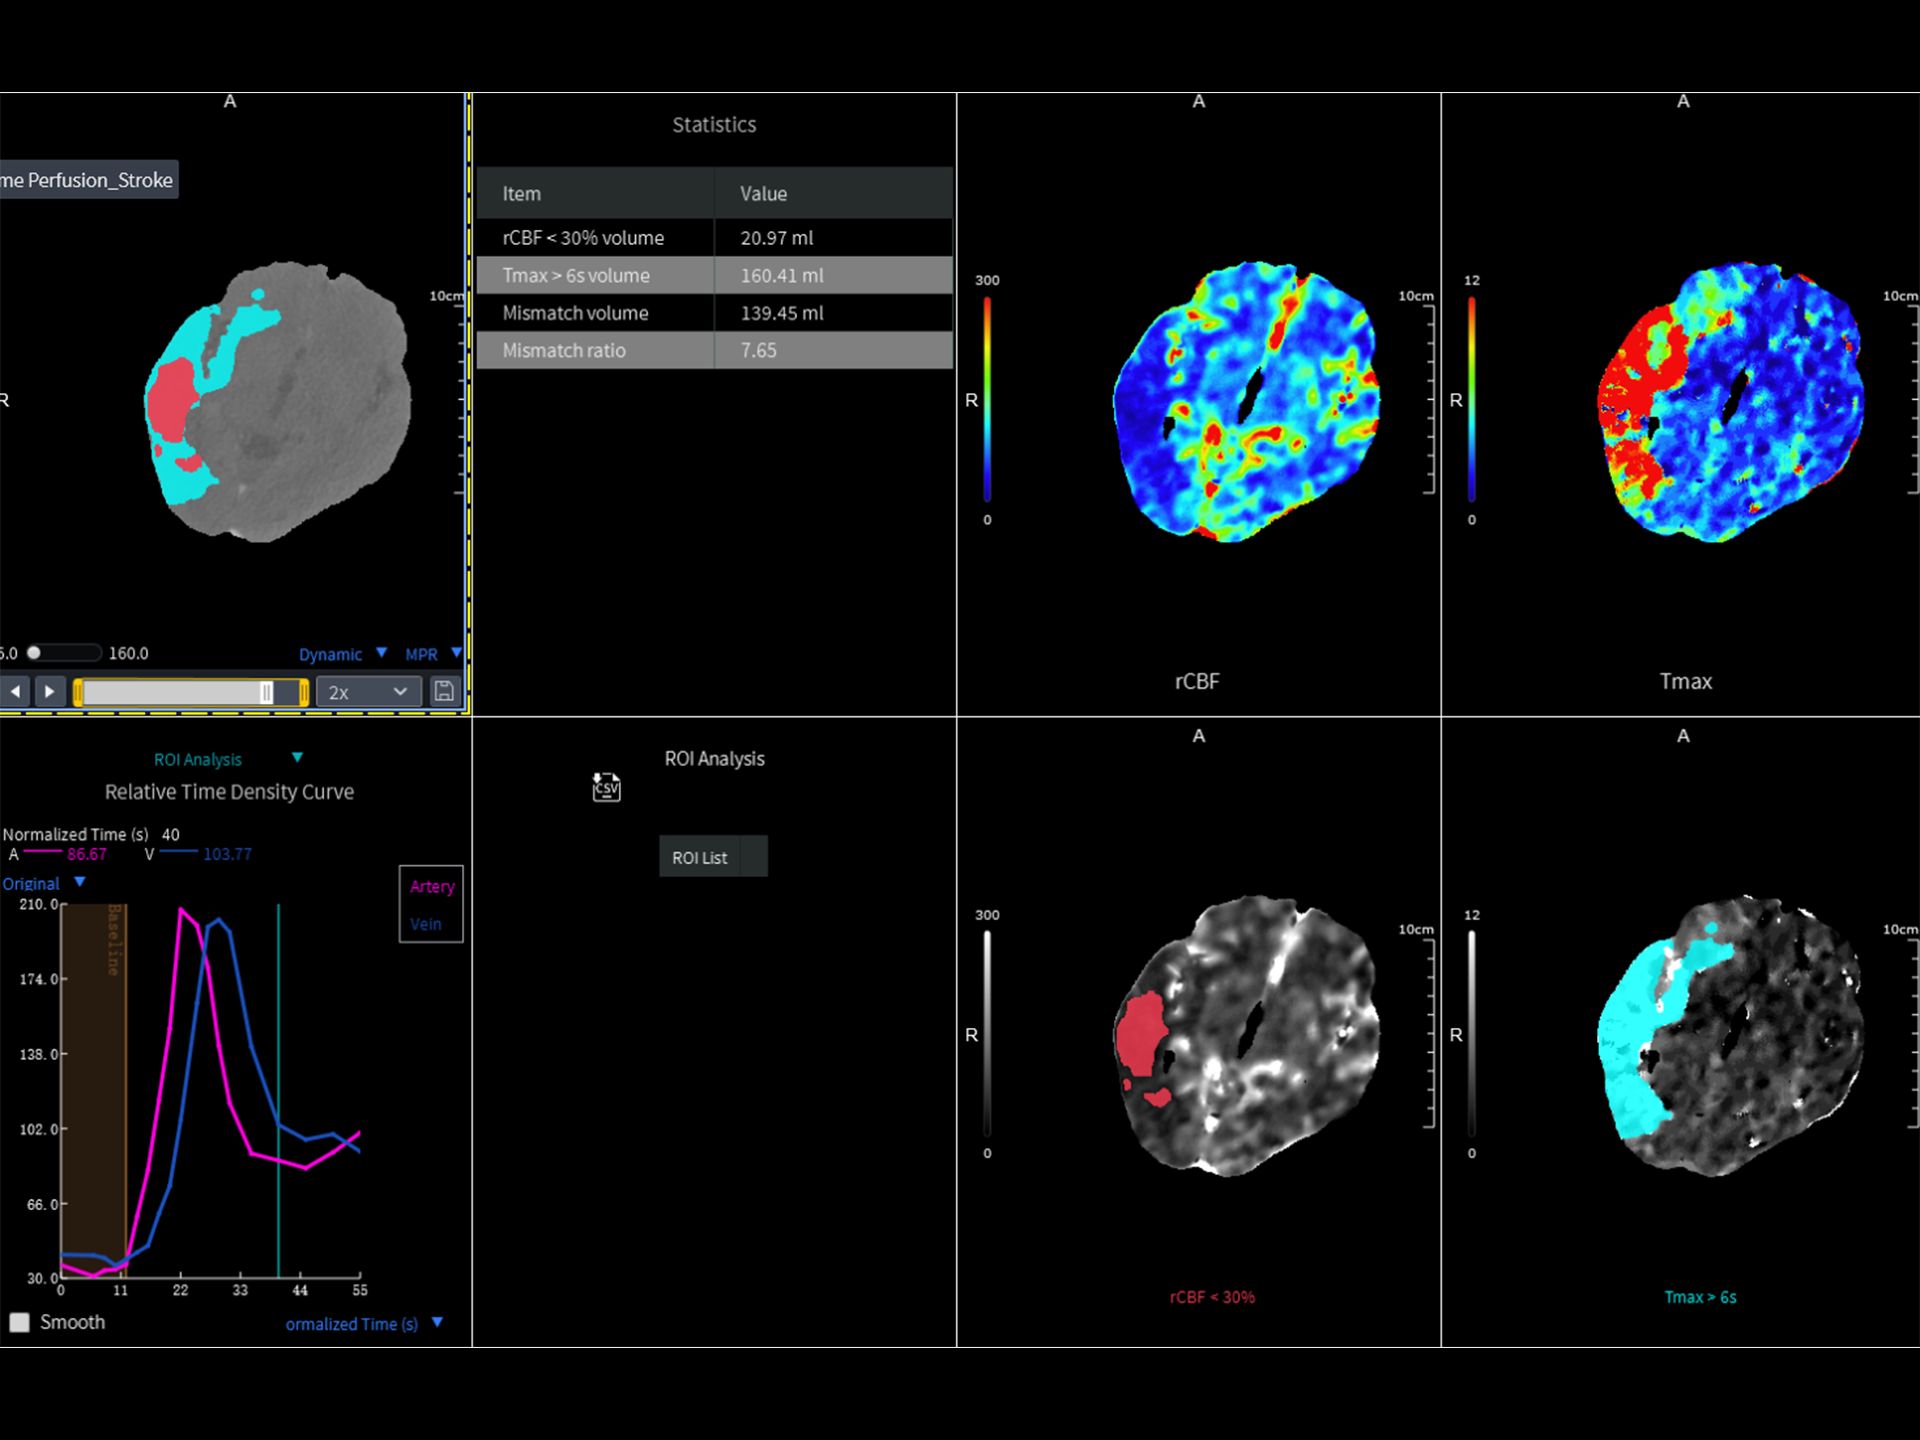

随着急性缺血性卒中血管内治疗的快速发展,神经影像,尤其是多模态CT成像在卒中分诊与治疗决策中的关键作用日益凸显。其中,CT灌注作为一种快速且实用的评估手段,能够动态反映脑部灌注状态的时间演变,帮助识别可挽救的高危半暗带组织与不可逆的梗死核心。通过快速测量与结果输出,CT灌注为临床争取宝贵治疗窗口提供了坚实支撑。

相较于传统 4–8 cm 的局部灌注扫描,受限的覆盖范围可能导致关键脑区信息缺失,影响诊断完整性。uCT 868 配备 180 mm 动态灌注技术,搭配多参数后处理分析软件,全面提升卒中评估的精准性与效率。

脑灌注分析可在加载数据后自动执行工作流操作并显示灌注分析结果,用于检测疑似中风患者的缺血性变化。该应用提供自动的参数计算,包含CBV、CBF、MTT、TTP、PS、Tmax、rCBV、rCBF、rMTT,并通过参数计算自动生成缺血半暗带及核心梗死区伪彩显示。除此之外,可根据用户绘制的ROI生成时间密度曲线,并生成统计表格。

全脑灌注卒中解决方案

18cm全脑灌注

脑灌注智能分析*